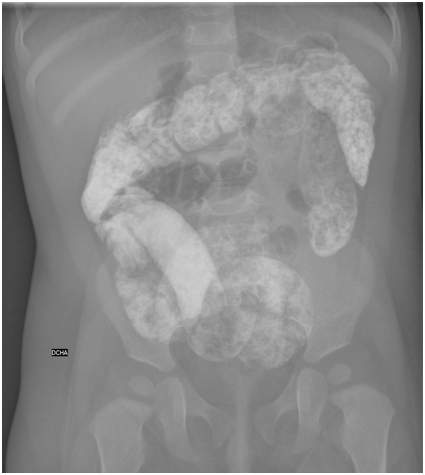

We present the case of a previously healthy 9-month-old infant who went to the Emergency Department due to a 7-hour evolution of paroxysms of abdominal pain with vegetative symptoms that alternated with hypoactivity and progressive lethargy. Anorexia and vomiting were also associated, fever was absent and the last stool was 12 hours prior, with normal characteristics. Vital signs were normal. On physical examination, the involvement of the general state with obtundation was noteworthy. The meningeal signs were negative, and there was no neurological focality. The abdomen was painful and presented tenderness on the right flank without signs of peritonism. Blood analysis was normal, and urine was negative for toxins. Abdominal radiograph revealed abundant radiopaque material in the small and large intestines without signs of intestinal perforation or pneumatosis (Figure 1). Abdominal ultrasonography confirmed ileocolic invagination. The parents denied the administration of contrast but reported copious sand intake 10 hours before the onset of symptoms. In view of the clinical suspicion of intestinal invagination secondary to massive sand intake, ultrasound guided hydrostatic reduction was performed. During the procedure, the symptoms suddenly ceased and the patient became asymptomatic. A large amount of sand was removed. Sand enteropathy due to ingestion of sand is rather common in horses.1 Geophagia is a form of pica considered normal in some cultures. Its aetiology is multifactorial and has been postulated as a marker of possible micronutrient deficit.2 One of its complications is intestinal obstruction and may be the point of origin of an intestinal intussusception.3-5

Figure 1 Simple abdominal radiography demonstrating the presence of radiopaque material in both distended distal ileum and normal-appearing colon in relation to massive sand intake.